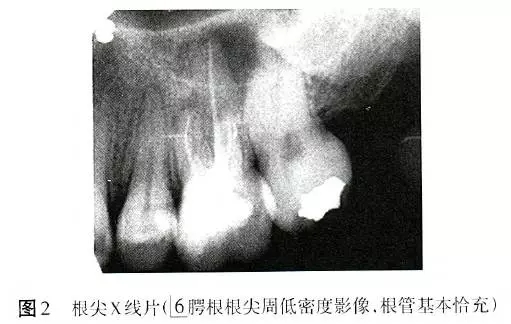

X線(xiàn)片顯示6根管恰充,腭根根尖周低密度影像,直徑6mm×6mm(圖2)。為排除根折,拍攝錐形束CT(CBCT),除發(fā)現(xiàn)MB2遺漏且未見(jiàn)明顯根折以外,意外發(fā)現(xiàn)6根尖周骨病損范圍遠(yuǎn)較X線(xiàn)片所顯示的更廣,累及全部牙根,且患牙頰側(cè)硬骨板缺損(圖3)。診斷:6根管治療后疾?。╬ost-treatment endodontic disease,PTED)。